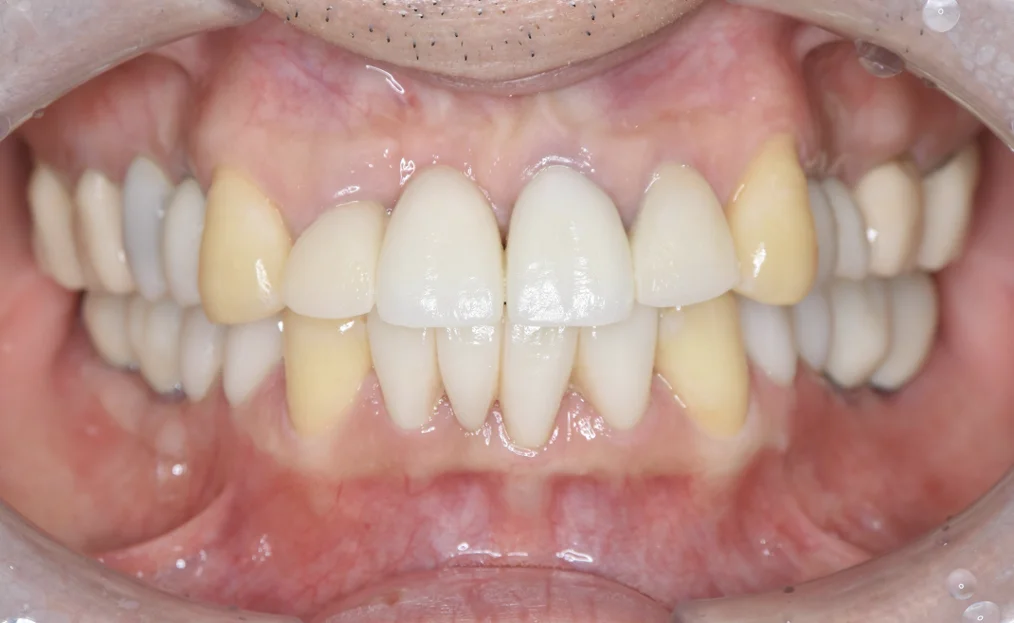

矯正治療の成功には、「見た目」だけでなく、「機能性」が伴っていることが重要です。

矯正治療によって噛み合わせが整うと、歯への過度な負担が軽減され、虫歯や歯周病のリスクも低下します。

また、咬合の安定は、顎関節症の予防や改善、姿勢・発音・呼吸・睡眠といった日常の機能にも好影響を与える可能性があります。

当院には「噛み合わせの認定医」も在籍し、必要に応じて咬み合わせの調整をご提案して調整を施すことで、矯正後の安定性を高めることができます。

「誰もが本当に喜べる矯正を提供したい」という治療目標を掲げる当院では、その実現のため、単に綺麗な歯並びに整えるだけでなく、原因の部分をきちんと治して、矯正後の咬み合わせの違和感や体調の変化を最小限に抑える治療を行なっています。